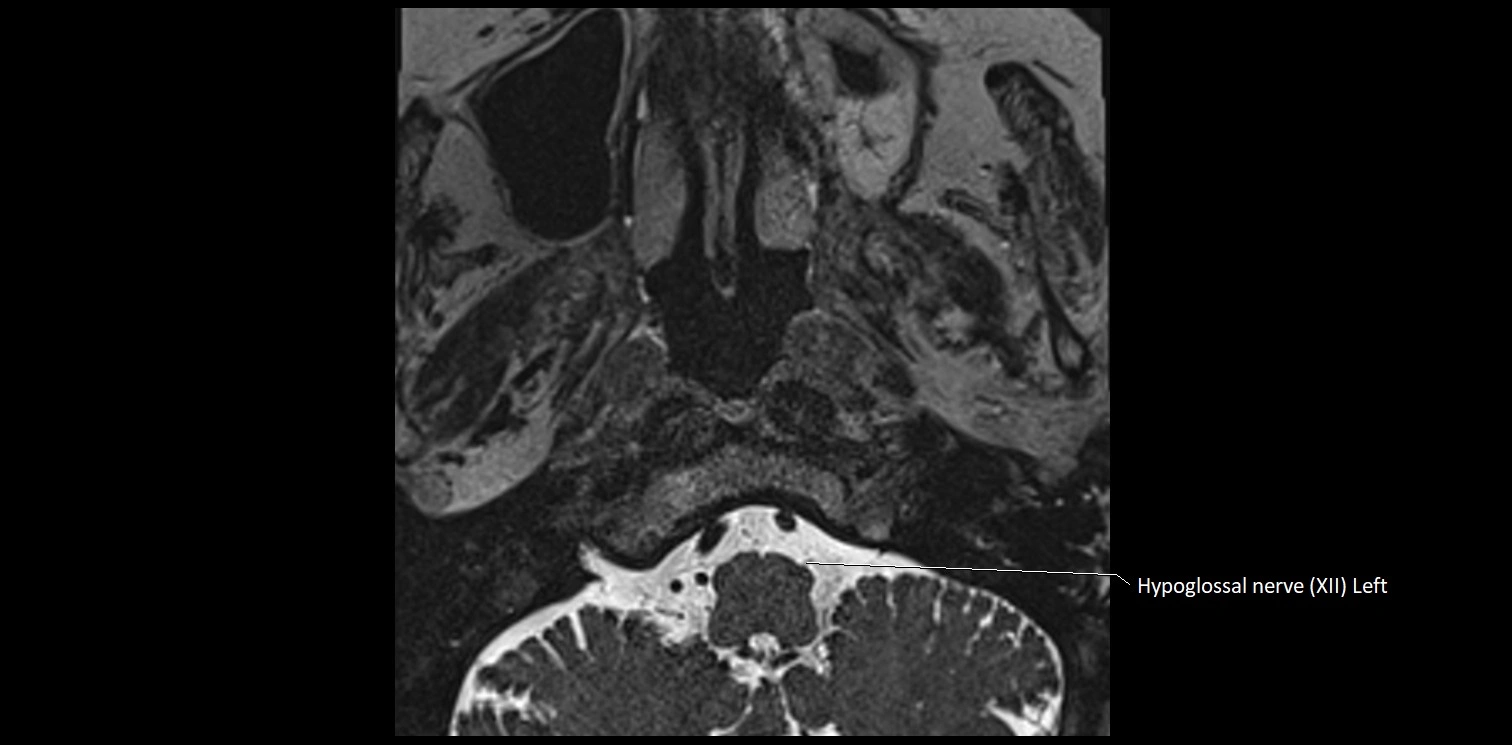

MRI images

image